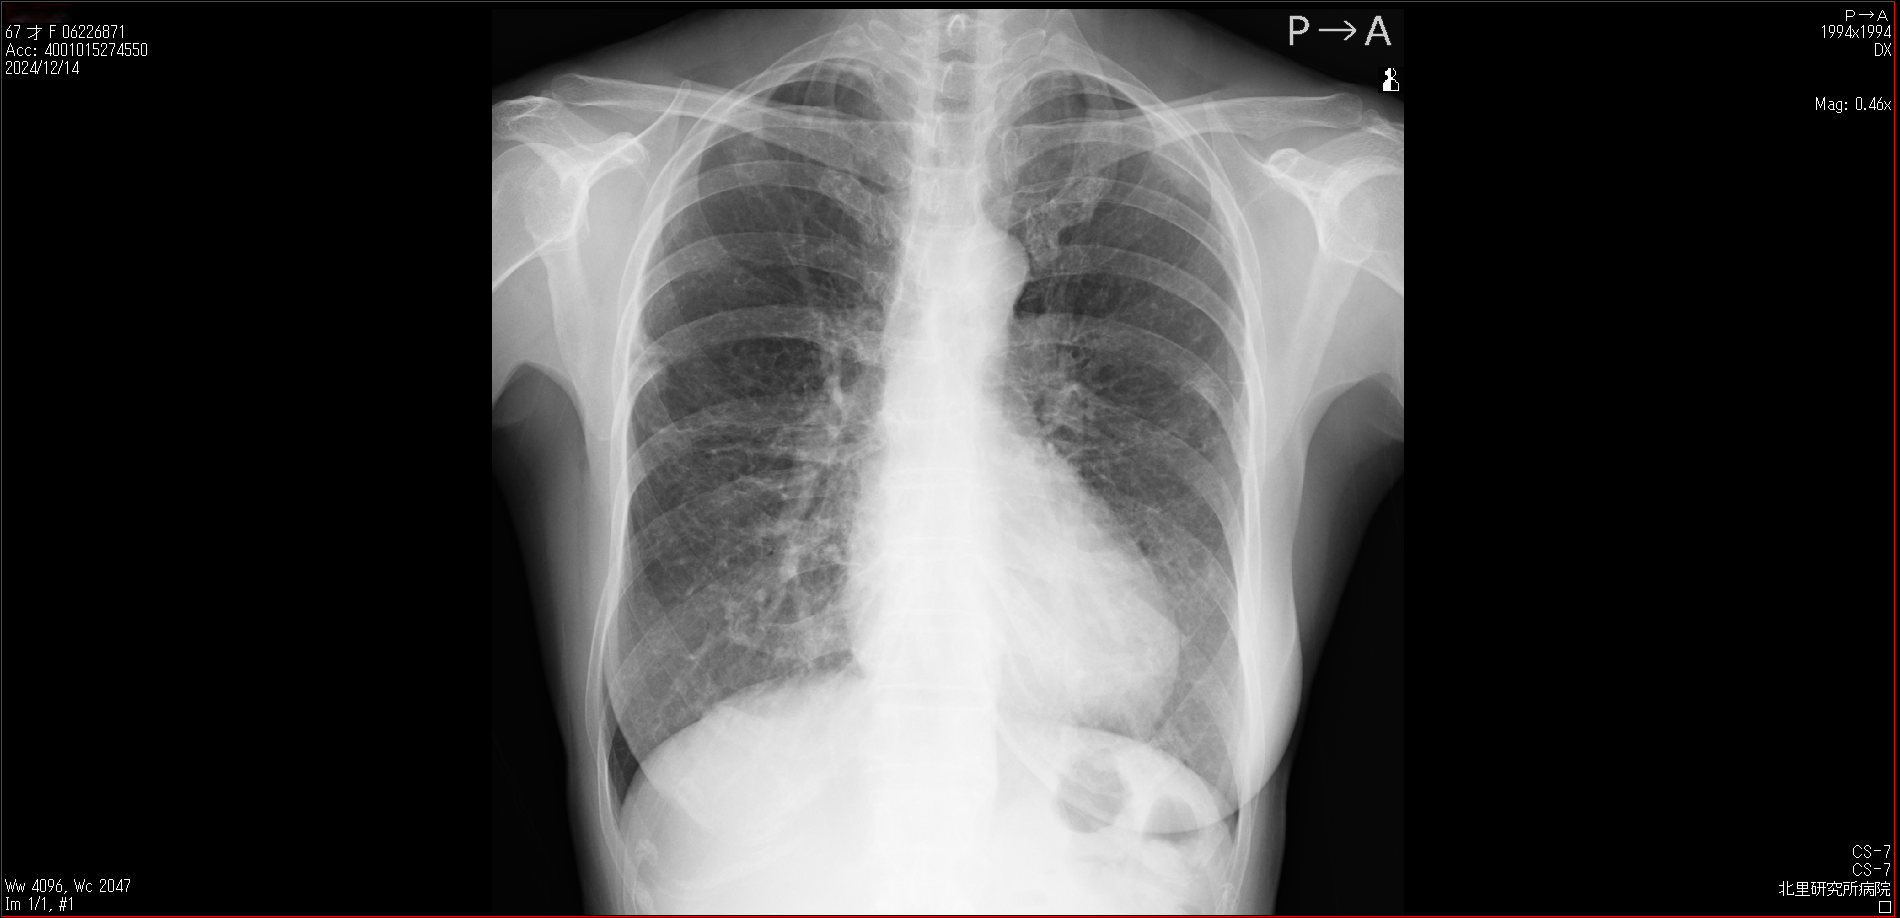

- 2024.12.14 転院後の要観察(4)(私立の病院Z)